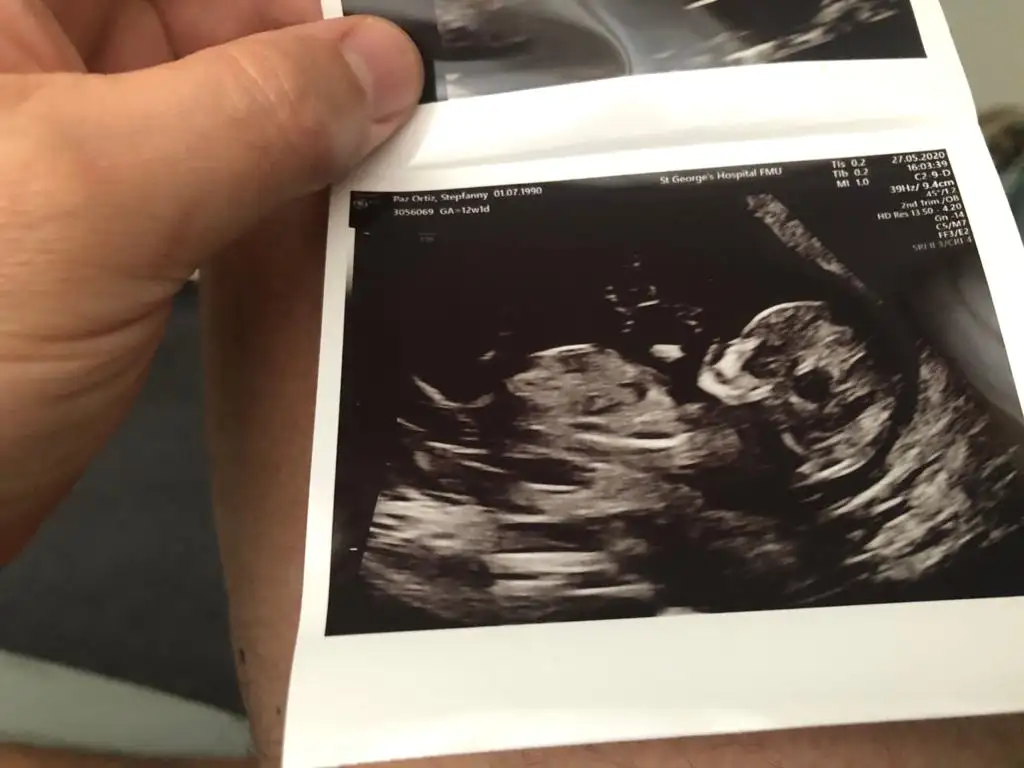

Şimdilik kız sanki dr nubuna + getirmiş emin olmadım başka usgde paylaşın 13 hafta olursaTahminlerinizi alabilir miyiz11+4

Teşekkür ederim bakalim olursa paylaşırım tabiiŞimdilik kız sanki dr nubuna + getirmiş emin olmadım başka usgde paylaşın 13 hafta olursa

Kaç hafta usg 11 12 13 hafta olmalı sanki kız ama emin olamadım başka usg varsa paylaşınBuda benim bebeğim eğer bakarsanız sevinirim Allahım sağlıkla versin kucaklarımıza merak etim 3 hafta sonra öğreneceğiz cinsiyetini şimdiden teşekkür ediyorum

Nubu kız görünüyor kafa şekli erkek görünüyorEki Görüntüle 2645670